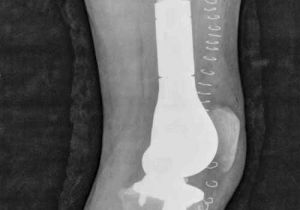

मासूम के दाएं पैर में घुटने के ऊपर था कैंसर, डॉक्टरों ने मेगा प्रोस्थेसिस लिम्ब सॉल्वेज सर्जरी कर पैर कटने से बचाया

6 May, 2023 12:18 PM IST | ASIAVARTANEWS.COMरायपुर हाल ही में डॉ. भीमराव अम्बेडकर स्मृति चिकित्सालय के अस्थि रोग विभाग में डॉक्टरों की...